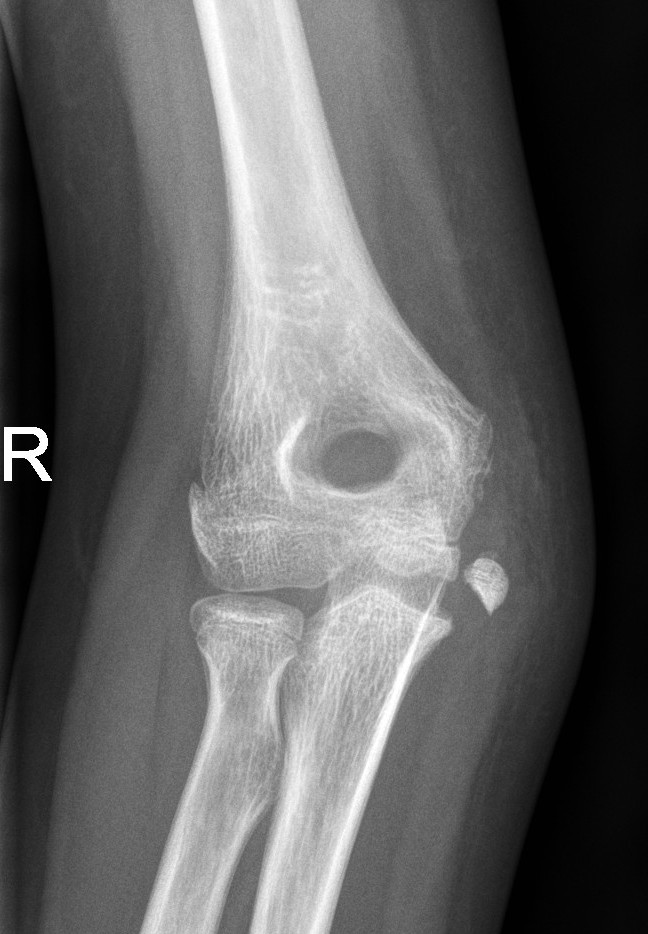

Olecranon fractures

- Olecranon fractures are often seen in combination with other elbow fractures (lateral condyle, supracondylar, radial neck or radial head dislocation).

Undisplaced olecranon fractures

- Above elbow plaster backslab at 90 degrees flexion with Orthopaedic Fracture clinic follow up in 7-10 days.

Displaced olecranon fractures

- Should be discussed with the Orthopaedic team for further management.

Non-displaced Olecranon fracture

Radial Head and Neck Fractures (Proximal Radius)

- Minimally displaced radial head and neck fractures with < 30 degrees angulation

- Displaced fractures or > 30 degrees angulation

- should be discussed with the Orthopaedic team for reduction.

Radial neck fracture